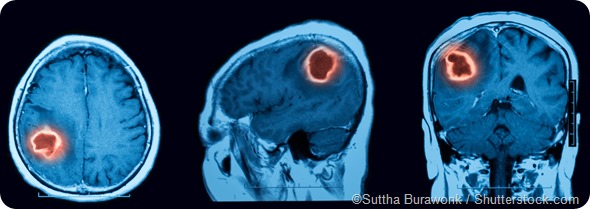

When symptoms of ICH are observed, neuroimaging should be carried out as quickly as possible - usually CT or MRI are performed. A lumbar puncture or CT angiography may also be necessary to confirm the diagnosis. Treatments include supportive care, reversal of anticoagulation therapy and surgical evacuation.